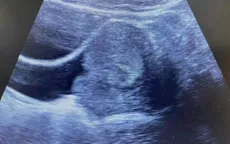

Dây rốn thắt nút nguy hiểm thế nào với thai nhi?

VTV.vn - Dây rốn thắt nút là hiện tượng dây rốn tự tạo thành nút thắt bên ngoài trong quá trình thai xoay chuyển vận động trong buồng ối.